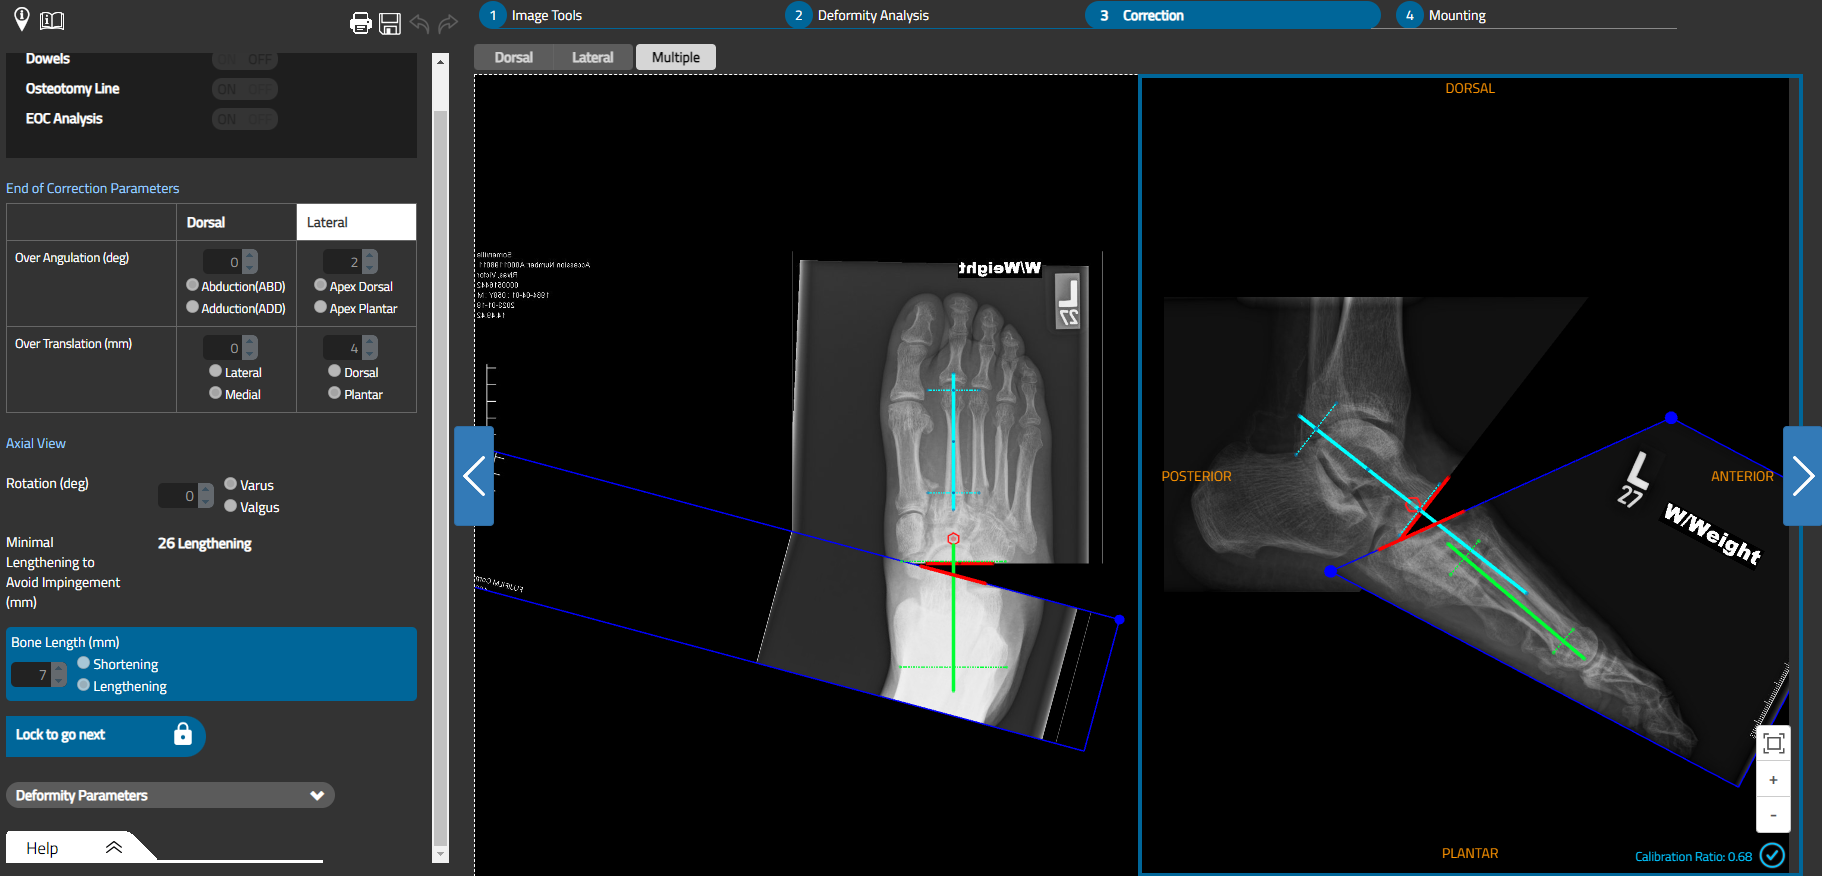

Stage 1: Application of external fixation. Surgical planning starts with entering data into the TL-Hex software. As with most programs, you must enter the case information, including case type (deformity or fracture), laterality, bone type, etc. Then one chooses the reference segment, which is typically proximal when addressing the midfoot Charcot deformity. There are then 2 methods to enter the deformity parameters: manual input of the required values (ie, angular measurements), and uploading radiographic images into the software. Two orthogonal (90°) images are required (ie, AP and lateral views) with any protected health information redacted, but the ruler must be included, as it is necessary for calibration. You will then need to calibrate the measurements of the image.

One may superimpose the calibration tool on the ruler and enter the value (ie, 40 mm) into the dialogue box. You will then be asked to determine the reference axis and moving axis, which will then provide you with the apex of the deformity where one would typically place the osteotomy. Select the ring diameter, followed by the latency period and correction rate. Latency is generally between 5–14 days, depending on patient comorbidities, and correction is typically 1mm/day. After inputting all values, the software will produce a visual representation of the corrected deformity as well as a plan that includes the length and color of each strut and their orientation on the rings. The system will create a daily strut adjustment program.